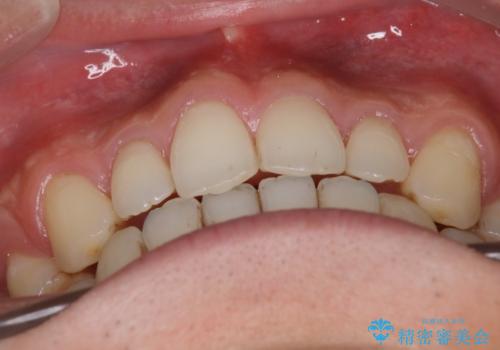

- 上の前歯の隙間と口元を下げたとのことで来院されました。

上顎正中離開と、口唇の突出感がありました。

上下左右の歯を1本ずつ抜歯しして、上顎の前歯を後方に移動させるのと、正中の隙間を閉じる計画としました。

装置はなるべく目立たないものをご希望でしたので、ハーフリンガルを選択されました。

抜歯をせず上顎の正中離開のみの矯正もできましたが、患者様と相談して口元の改善も同時に行うために抜歯矯正の計画としました。